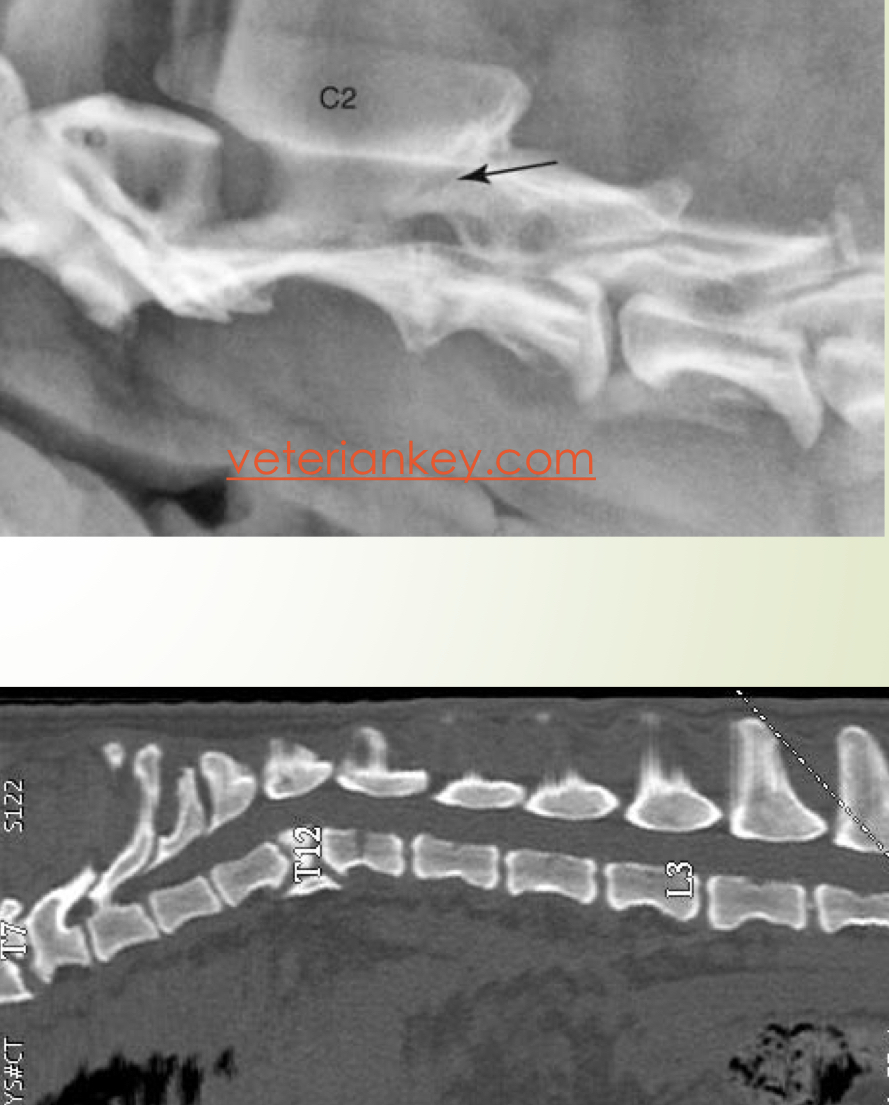

Anormalidades congénitas

Anormalidades vertebrales :

* Hemivértebra (braquicefalicos)

* Fusión vertebral

Subluxación atlantoaxial

Espina bifida

La mayoría de las veces no dan signos clinicos →Para confirmar que son la causa de los déficits : mielografia, mielotac o RM

Fallo núcleo osificación

A

Forma de cuña

Tipo :

* Lateral : escoliosis

* Dorsal : cifosis

* Ventral : lordosis

• Inestabilidad de la articulación por hipo/aplacia o fractura del diente del axis

• Excesiva flexión de la art. atlantoaxial

• Compresión del canal medular

SC :

* Normalmente < 1 año (!hasta 9 año)

* Lesion en c1-c5 :

1° Dolor → Ataxia → Tetraparesis → Tetraplejia y muerte

DX : rx simple !!!!OJO, flexionar un poquito

TTO :

* Quirurgico : 80% exito - 15% mortalidad perioperatoria

* Inmobilizacion : si solo hay dolor, sin deficit neuro, 55% exito